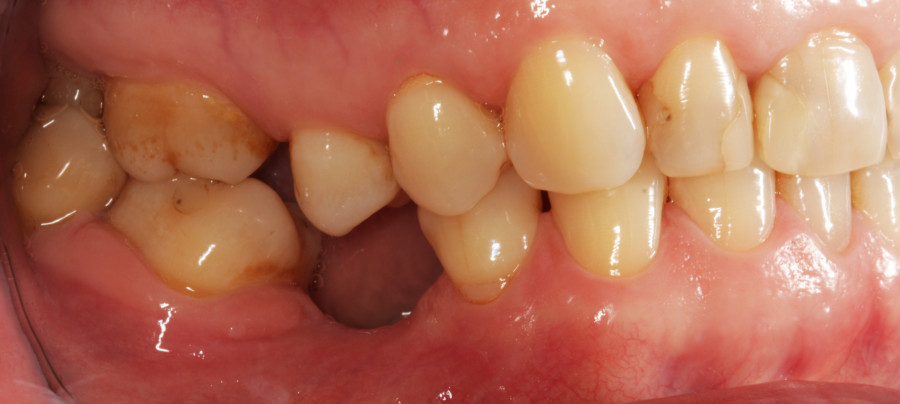

Do kliniki Stomatologia Bez Bólu zgłosiła się pacjentka, lat 61 z problemem nadwrażliwości zębów. Po przeprowadzonym wywiadzie stwierdzono spożywanie sporej ilości sezonowych owoców (truskawki, wiśnie, czereśnie, czarna porzeczka), nawet 3 razy dziennie. Następnie wykonano badanie wewnątrzustne. Stwierdzono obecność płytki nazębnej, ciemnego osadu oraz kamienia nazębnego na części trzonowców:

Wykonano higienizację jamy ustnej poprzez usunięcie kamienia nazębnego skalerem ultradżwiękowym, zdjęciem osadu i płytki nazębnej poprzez piaskowanie air flow plus oraz classic, a następnie wypolerowaniu gumką ze specjalistyczną pastą polerską: